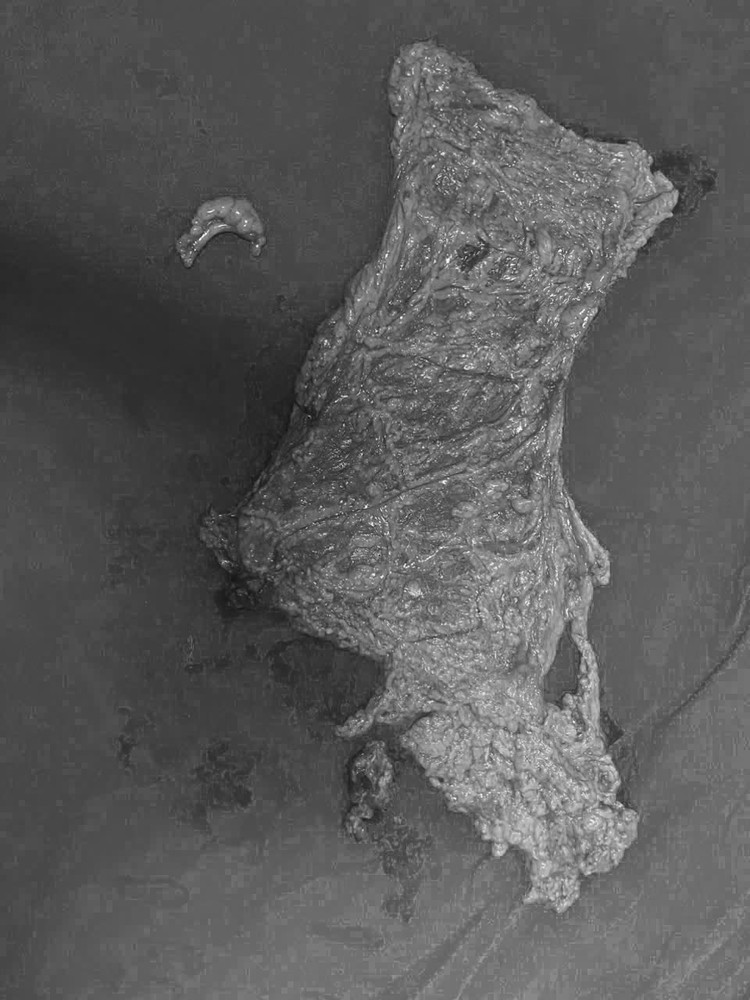

| Khối u này lại giàu mạch máu nuôi dưỡng nên nguy cơ chảy máu rất cao, gây nhiều khó khăn trong việc phẫu thuật. Ảnh BVCC |

Theo các bác sĩ, đây là một ca phẫu thuật khó vì bệnh nhân nhiều bệnh lý nền, mặt khác khối u kích thước lớn đã làm biến đổi giải phẫu các cấu trúc trong tiểu khung như: Niệu quản, bàng quang, trực tràng, động mạch chậu… Ngoài ra, khối u này lại giàu mạch máu nuôi dưỡng nên nguy cơ chảy máu rất cao, gây nhiều khó khăn trong việc phẫu thuật.

Các bác sĩ đã phải thực hiện phẫu tích tỉ mỉ, bóc tách và bảo tồn được các cấu trúc quan trọng trong cuộc mổ. Sinh thiết tức thì cho kết quả ung thư buồng trứng, Ekip phẫu thuật đã tiến hành cắt toàn bộ, hai phần phụ kèm mạc nối lớn, ruột thừa và khối u.